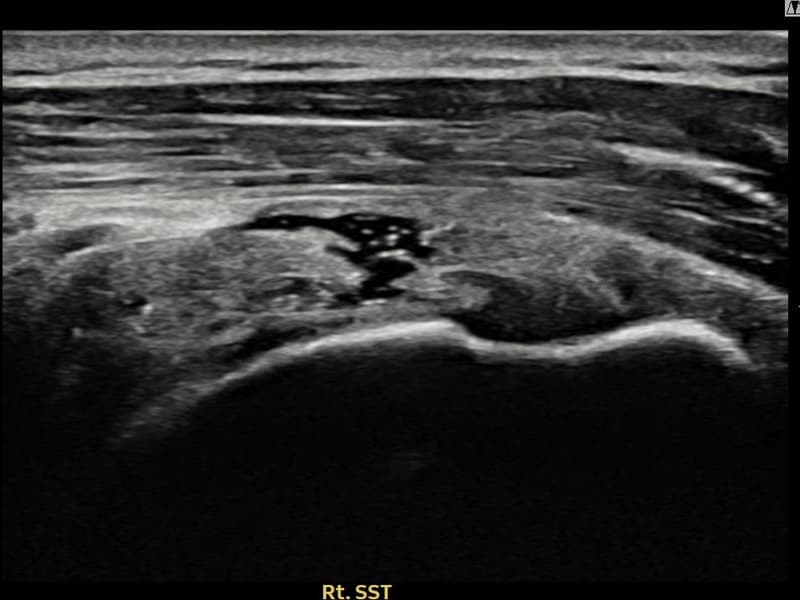

시술 전 초음파 측정 결과 파열 크기는 9mm × 4mm (힘줄 두께의 약 38% 결손)로 확인되었습니다. 시술 전 초음파에서 우측 극상근건 내 에코 단절과 함께 건내 고에코 석회화 소견이 동반 확인되었습니다. 시술 후 초음파에서 파열 부위의 연속성이 회복되고 석회화 부위의 에코 패턴이 개선된 것이 관찰되었습니다.

50대 후반 여성 환자분으로, 야간 통증이 극심하여 어깨를 아래로 향하고 자도 통증이 느껴지는 상태로 내원하셨습니다. 초음파 검사에서 극상근건 부분파열과 함께 건내 석회화가 동반된 복합 소견이 확인되었습니다. 석회화와 파열이 함께 존재하는 경우 충격파만으로는 힘줄 구조 회복이 어려워 초음파 유도 하 축소봉합술을 선택하였습니다. 시술은 30여 분에 완료되었고 당일 귀가 가능하셨으며, 이후 보조기를 착용하며 단계적 재활을 진행하였습니다. 시술 11주 후 추적 초음파에서 파열 부위 연속성 회복과 함께 석회화 소견도 뚜렷이 감소한 것이 확인되어 야간 통증 없이 정상 생활에 복귀하셨습니다.